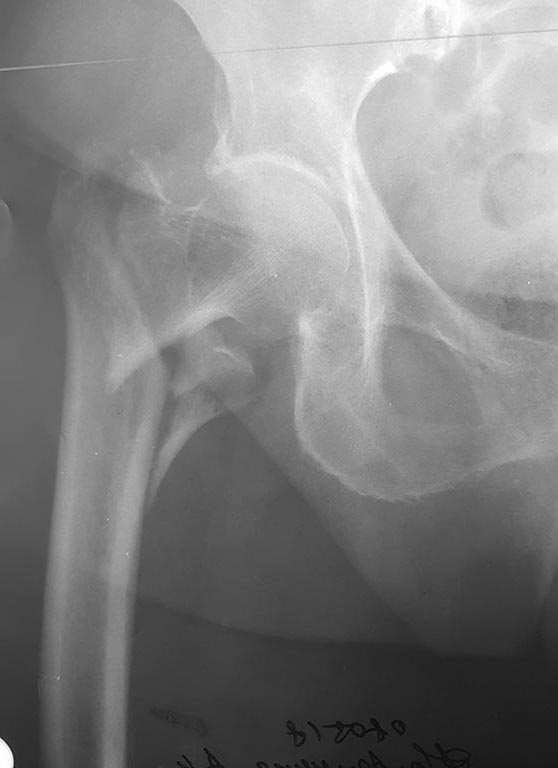

[Ortho] БИОС PFNA варусного бедра

Первичный снимок